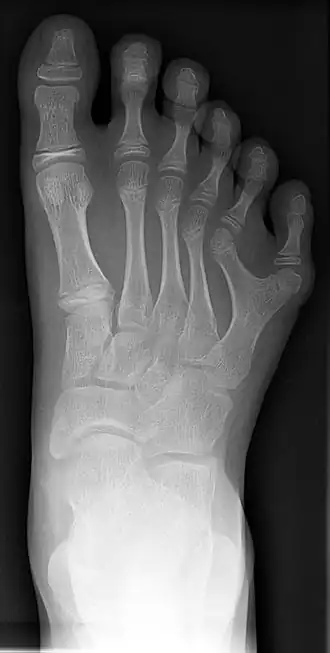

Röntgenfoto van hand met 6 vingers -

Röntgenfoto van voet met 6 tenen